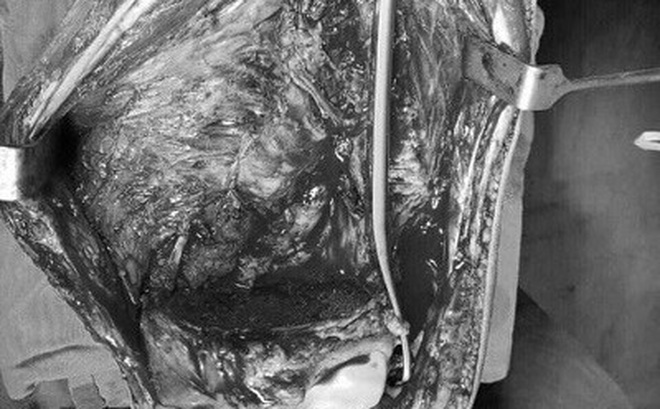

Chia sẻ về ca bệnh PGS. TS. Trần Trung Dũng - Phó Giám đốc Bệnh viện Xanh Pôn, giảng viên trường Đại học Y Hà Nội- người mổ cho bệnh nhi T cho biết: Sau khi hội chẩn, bệnh nhi được tiến hành phẫu thuật, e kip phẫu thuật gồm nhiều chuyên gia của Viện K, Saint Paul và Đại Học Y Hà Nội, sau khi phẫu thuật lấy hết khối u ở đầu dưới xuong đùi, gần khớp gối cho bệnh nhi T.

Và sẽ được duy trì khoảng trống bằng xi măng sinh học và cố định bằng nẹp vít xương đùi. Sinh thiết tức thì trong mổ các diện cắt xương và phần mềm không còn tế bào ung thư. Bảo tồn được chức năng khớp gối và thẩm mỹ cho bệnh nhân.